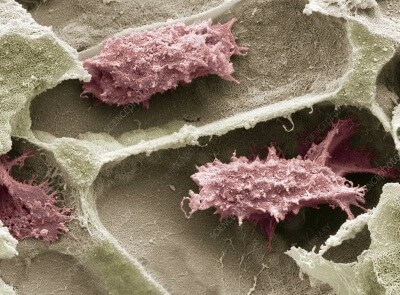

Замещение костных дефектов при удалении опухолей и опухолевидных образований до настоящего времени является дискуссионной проблемой [1, 3, 4, 5]. Применение в качестве пластического материала ауто, алло и ксенотканей, а также их комбинаций не лишено ряда недостатков [4, 6]. Среди биоматериалов, способных перестраиваться и обладающих остеоиндуктивными свойствами, наше внимание привлек предложенный нам фирмой "Конектбиофарм" для клинического апробирования материал нового поколения "Остеоматрикс", на основе костного аллоколагена, костных аллоглюкозаминогликанов и гидроксиаппатита [2, 4]. Материал получил широкое применение в практике травматологии, ортопедии и стоматологии России [2, 3 ].

Согласно проведенных клинических испытаний "Остеоматрикс" характеризуется хорошей биоинтеграцией, высокой биосовместимостью и способностью осуществлять биоиндуктивную функцию.

Костную полость заполняли гранулами остеоматрикса размером 0,2 – 0,3 мм. Учитывая свойство "Остеоматрикса" изменять конфигурацию гранул в условиях жидкой среды тканевого детрита, заполнение полости в соответствии с ее формой не представляло технических трудностей. Умеренно выраженная тенденция набухания коллагена обеспечивает условия плотного его прилегания к стенкам костной полости.

Результаты проведенного исследования подтверждают, что биокомпозитный материал "Остеоматрикс" при помещении его в костный дефект способствует построению собственной костной ткани у больных с кистами фаланг пальцев кисти. Формирование плотной субстанции, согласно рентгенограмм происходит в сроки от 3 до 6-ти месяцев. Таким образом "Остеоматрикс" может использоваться для замещения костных дефектов как самостоятельный пластический материал, так и в сочетании с аутокостью.